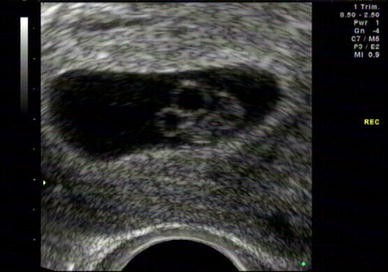

The purpose of the scan is to confirm viability, accurately establish gestational age, determine the number of viable fetuses, evaluate gross fetal anatomy and, if requested, assess the NT as part of the risk assessment for aneuploidy . Indications for early pregnancy scans (less than 12 weeks) Indications include:

The following screening examinations are part of routine primary maternity care in New Zealand and should be offered to all women: 12-13-week scan ; 19+ week anatomy scan . Routine ultrasound should not be offered or requested to confirm an ongoing early pregnancy in the absence of any clinical concerns, symptoms or specific indications .

Pregnant women should be offered an early ultrasound scan between 10 + 0 and 13 + 6 weeks to establish accurate gestational age . (Grade A recommendation) Ultrasound assessment of embryonic/fetal age ( dating ) uses the following assumptions: